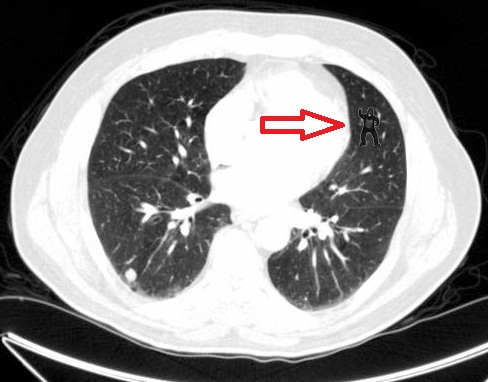

The researchers asked 24 radiologists to perform a familiar lung nodule detection task. They examined five scans; each scan contained an average of 10 nodules. A gorilla, 48 times larger than the average nodule, was inserted in the last scan. The researchers found that 83 percent of radiologists did not report seeing the gorilla. With the help of Melissa Le-Hoa Vo, post-doctoral researcher at BWH, the researchers tracked the eye-movements of the radiologists and found that that the majority of those who missed the gorilla looked directly at it.

“The radiologists missed the gorillas not because they could not see them, but because the way their brains had framed what they were doing. They were looking for cancer nodules, not gorillas,” explained Jeremy Wolfe, senior psychologist and director of the Visual Attention Laboratory at BWH. “This study helps illustrate that what we become focused on becomes the center of our world, and it shapes what we can and cannot see.”